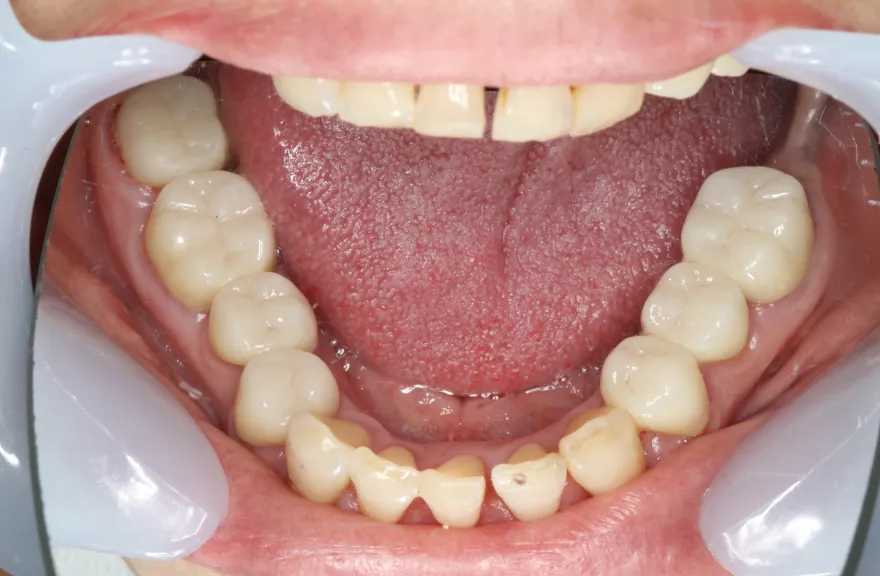

【治療例 2】金属を白くしたい63歳

- 相談内容

-

右上の奥歯が取れたということで来院されました。

各所の金属は昔に治療されたもので、外してみるとどれも虫歯になっていました。

一つずつ虫歯治療を行い、インプラント治療、矯正治療を並行して行いました。 - 治療費用・方針

写真の通りに治療を終了いたしました。

各所虫歯に侵食されていましたが、歯を残すことができたのでインプラントの数をおさえることができました。

下の前歯が先天的に1本欠損しており、そのため噛み合わせを構築することが難しいケースでした。矯正治療を併用することで前歯と奥歯をバランスよく噛ませることに成功しました。